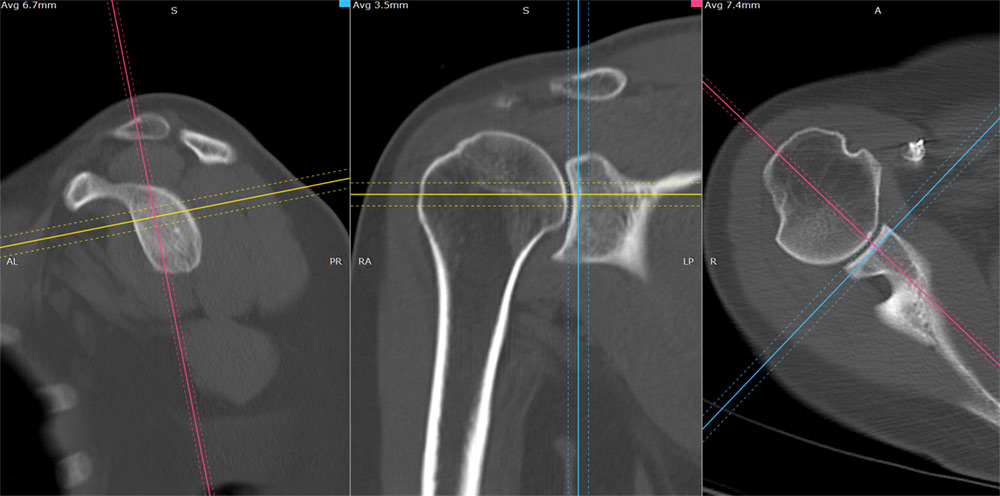

Reconstrucții în alte planuri (MPR)

Datele achiziționate la pasul 1 sunt în plan axial, însă pentru un diagnostic corect și ușor este nevoie și de reconstrucții în alte planuri decât cele axiale. Din acest motiv este foarte important în postprocesare ca operatorul să obțină reconstrucții în sagital și coronal (MPR – multiplanar reconstructions) pentru zona respectivă, care să respecte planurile corecte anatomic referitoare la acea articulație. În cazul umărului sagitalul va fi construit paralel cu cavitatea glenoidă, iar coronalul va fi perpedicular pe cavitatea aceasta.

Image

Aspect de reformatare în 3 direcții ale spațiului, reconstrucție MPR

În funcție de cerința medicului radiolog, după aceste reconstrucții multiplanare (MPR), operatorul ar trebui să realizeze secvențe MPR groase, în care prin însumarea planurilor să se poate urmări mai ușor o anumită structură, de exemplu un traiect de fractură.